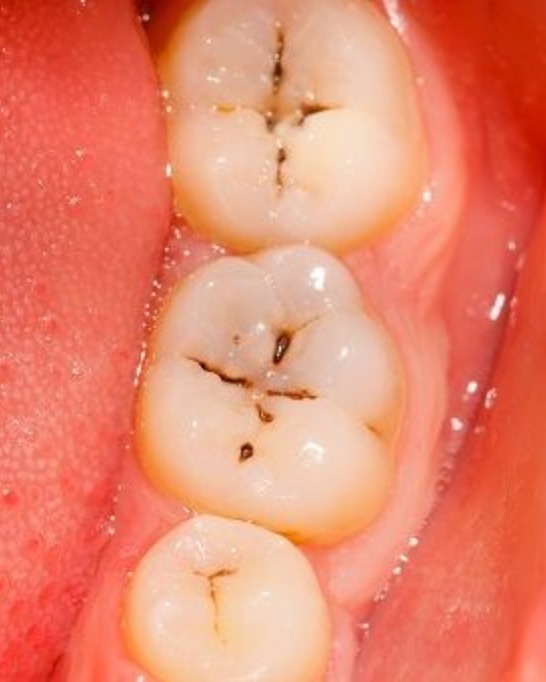

Dental cavity, also known as tooth decay or dental caries, is one of the most common oral health problems affecting both children and adults. It occurs when harmful bacteria in the mouth produce acids that gradually damage the tooth enamel due to frequent consumption of sugary foods, poor oral hygiene, and irregular dental check-ups. If left untreated, a cavity can progress deeper into the tooth, causing tooth pain, sensitivity to hot and cold foods, bad breath, and even infection. Early diagnosis is very important to prevent complications and preserve natural teeth. At Oasis Dental Care Chennai, dental cavity treatment is performed with advanced technology and painless procedures to ensure patient comfort. In the early stage, the decayed portion of the tooth is carefully removed and restored with high-quality tooth-colored fillings. If the decay has reached the inner pulp, Root Canal Treatment (RCT) is done to remove the infection and save the tooth, followed by placement of a dental crown for strength and protection. In severe cases where the tooth cannot be saved, safe tooth extraction and replacement options like dental implants or bridges are provided. If you are looking for the best dental clinic in Chennai for cavity treatment, Oasis Dental Care Chennai offers affordable dental care, experienced dentists, modern equipment, painless root canal treatment, tooth-colored fillings, and comprehensive oral health solutions. Regular dental check-ups, professional teeth cleaning, and proper oral hygiene can help prevent cavities and maintain a healthy, confident smile. #teeth_cavity #best_dental_clinic_chennai #oasis_dental_care#dental_clinic_arumbakkam